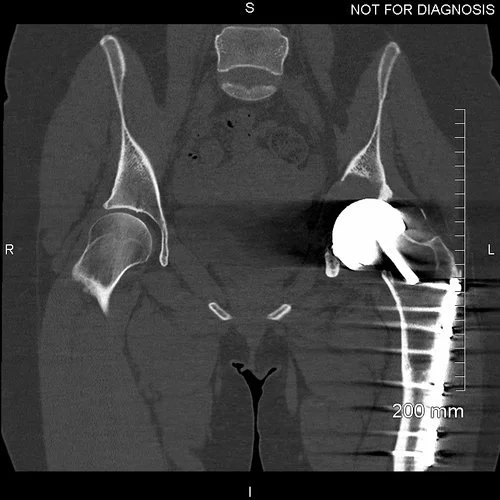

Coronal CT - This is used by the surgeon and the biomedical engineer to design the custom implant specifically to the patient’s acetabular bone stock. This CT demonstrates significant loss of bone stock relating to the left hip resurfacing.

3D CT reconstruction showing the hemipelvic defect.